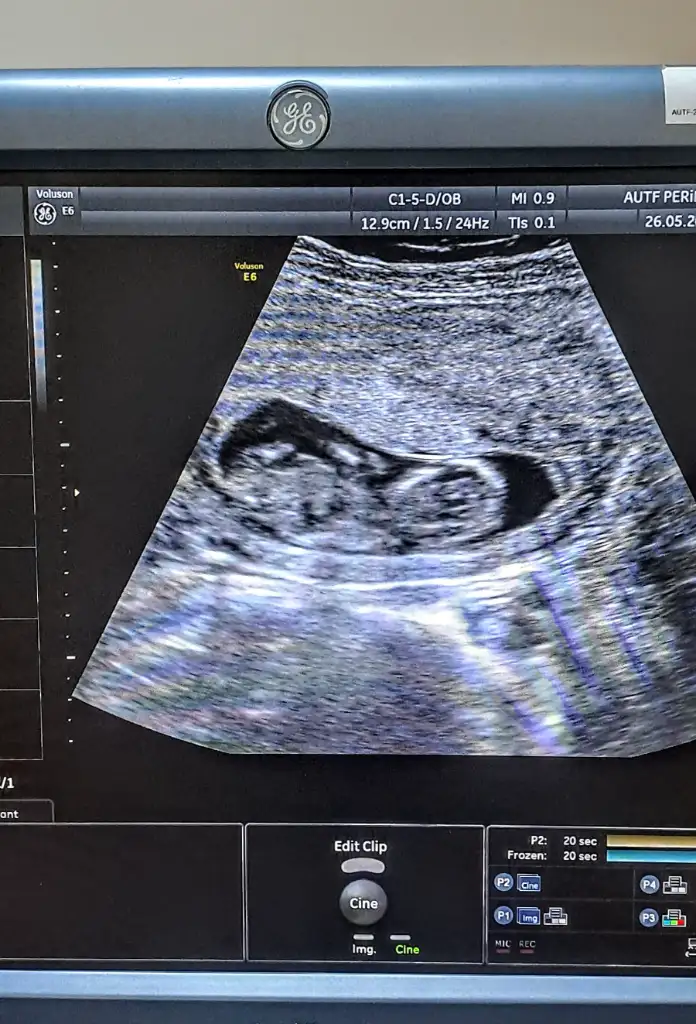

Kizlar siz anliyorsunuz galiba benimkine de bakar misiniz karindan ultrason

Erkek8+3 karından ultrasonla çekildi cinsiyet tahmini var mı

Kesenin üst tarafındaysa erkek diyorlar sizin de erkek buna göreKizlar siz anliyorsunuz galiba benimkine de bakar misiniz karindan ultrason